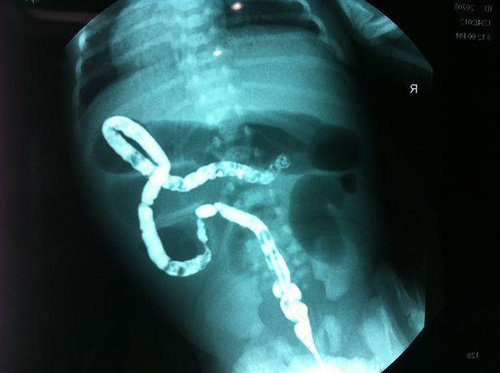

有些朋友经常肚子不舒服,例如腹痛腹胀,便秘,呕吐等等,怀疑是得了巨结肠。巨结肠是从形态学上对一个疾病的描述,可分为先天性巨结肠,假性先天性巨结肠和特发性巨结肠三种类型。那么得了巨结肠会腹痛吗?

巨结肠是会出现腹痛的,腹痛是巨结肠的一种中期症状。巨结肠的主要症状有消化不良,腹胀,排便习惯改变,便秘,腹泻,腹痛,严重的还有黏液便和黏血便。而腹痛的原因有可能是因为排便不畅导致肠管痉挛收缩,也有可能是排便困难与腹泻交替出现引起的腹痛。

巨结肠腹痛,是一种十分常见的临床症状。如果出现腹痛的症状,就需要通过一些药物来进行缓解。如果腹痛难忍,就应及时就医。一般情况下,巨结肠是需要手术治疗的,延误治疗有可能因为剧烈的腹胀而造成肠穿孔等,最终可能会恶化死亡。